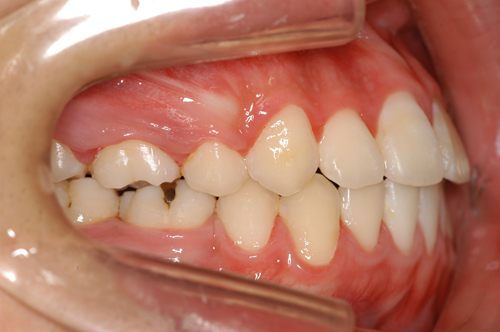

患者:14歳8ヶ月 男性

抜歯部位:上顎、第一小臼歯 下顎第二小臼歯

動的治療期間:18ヶ月